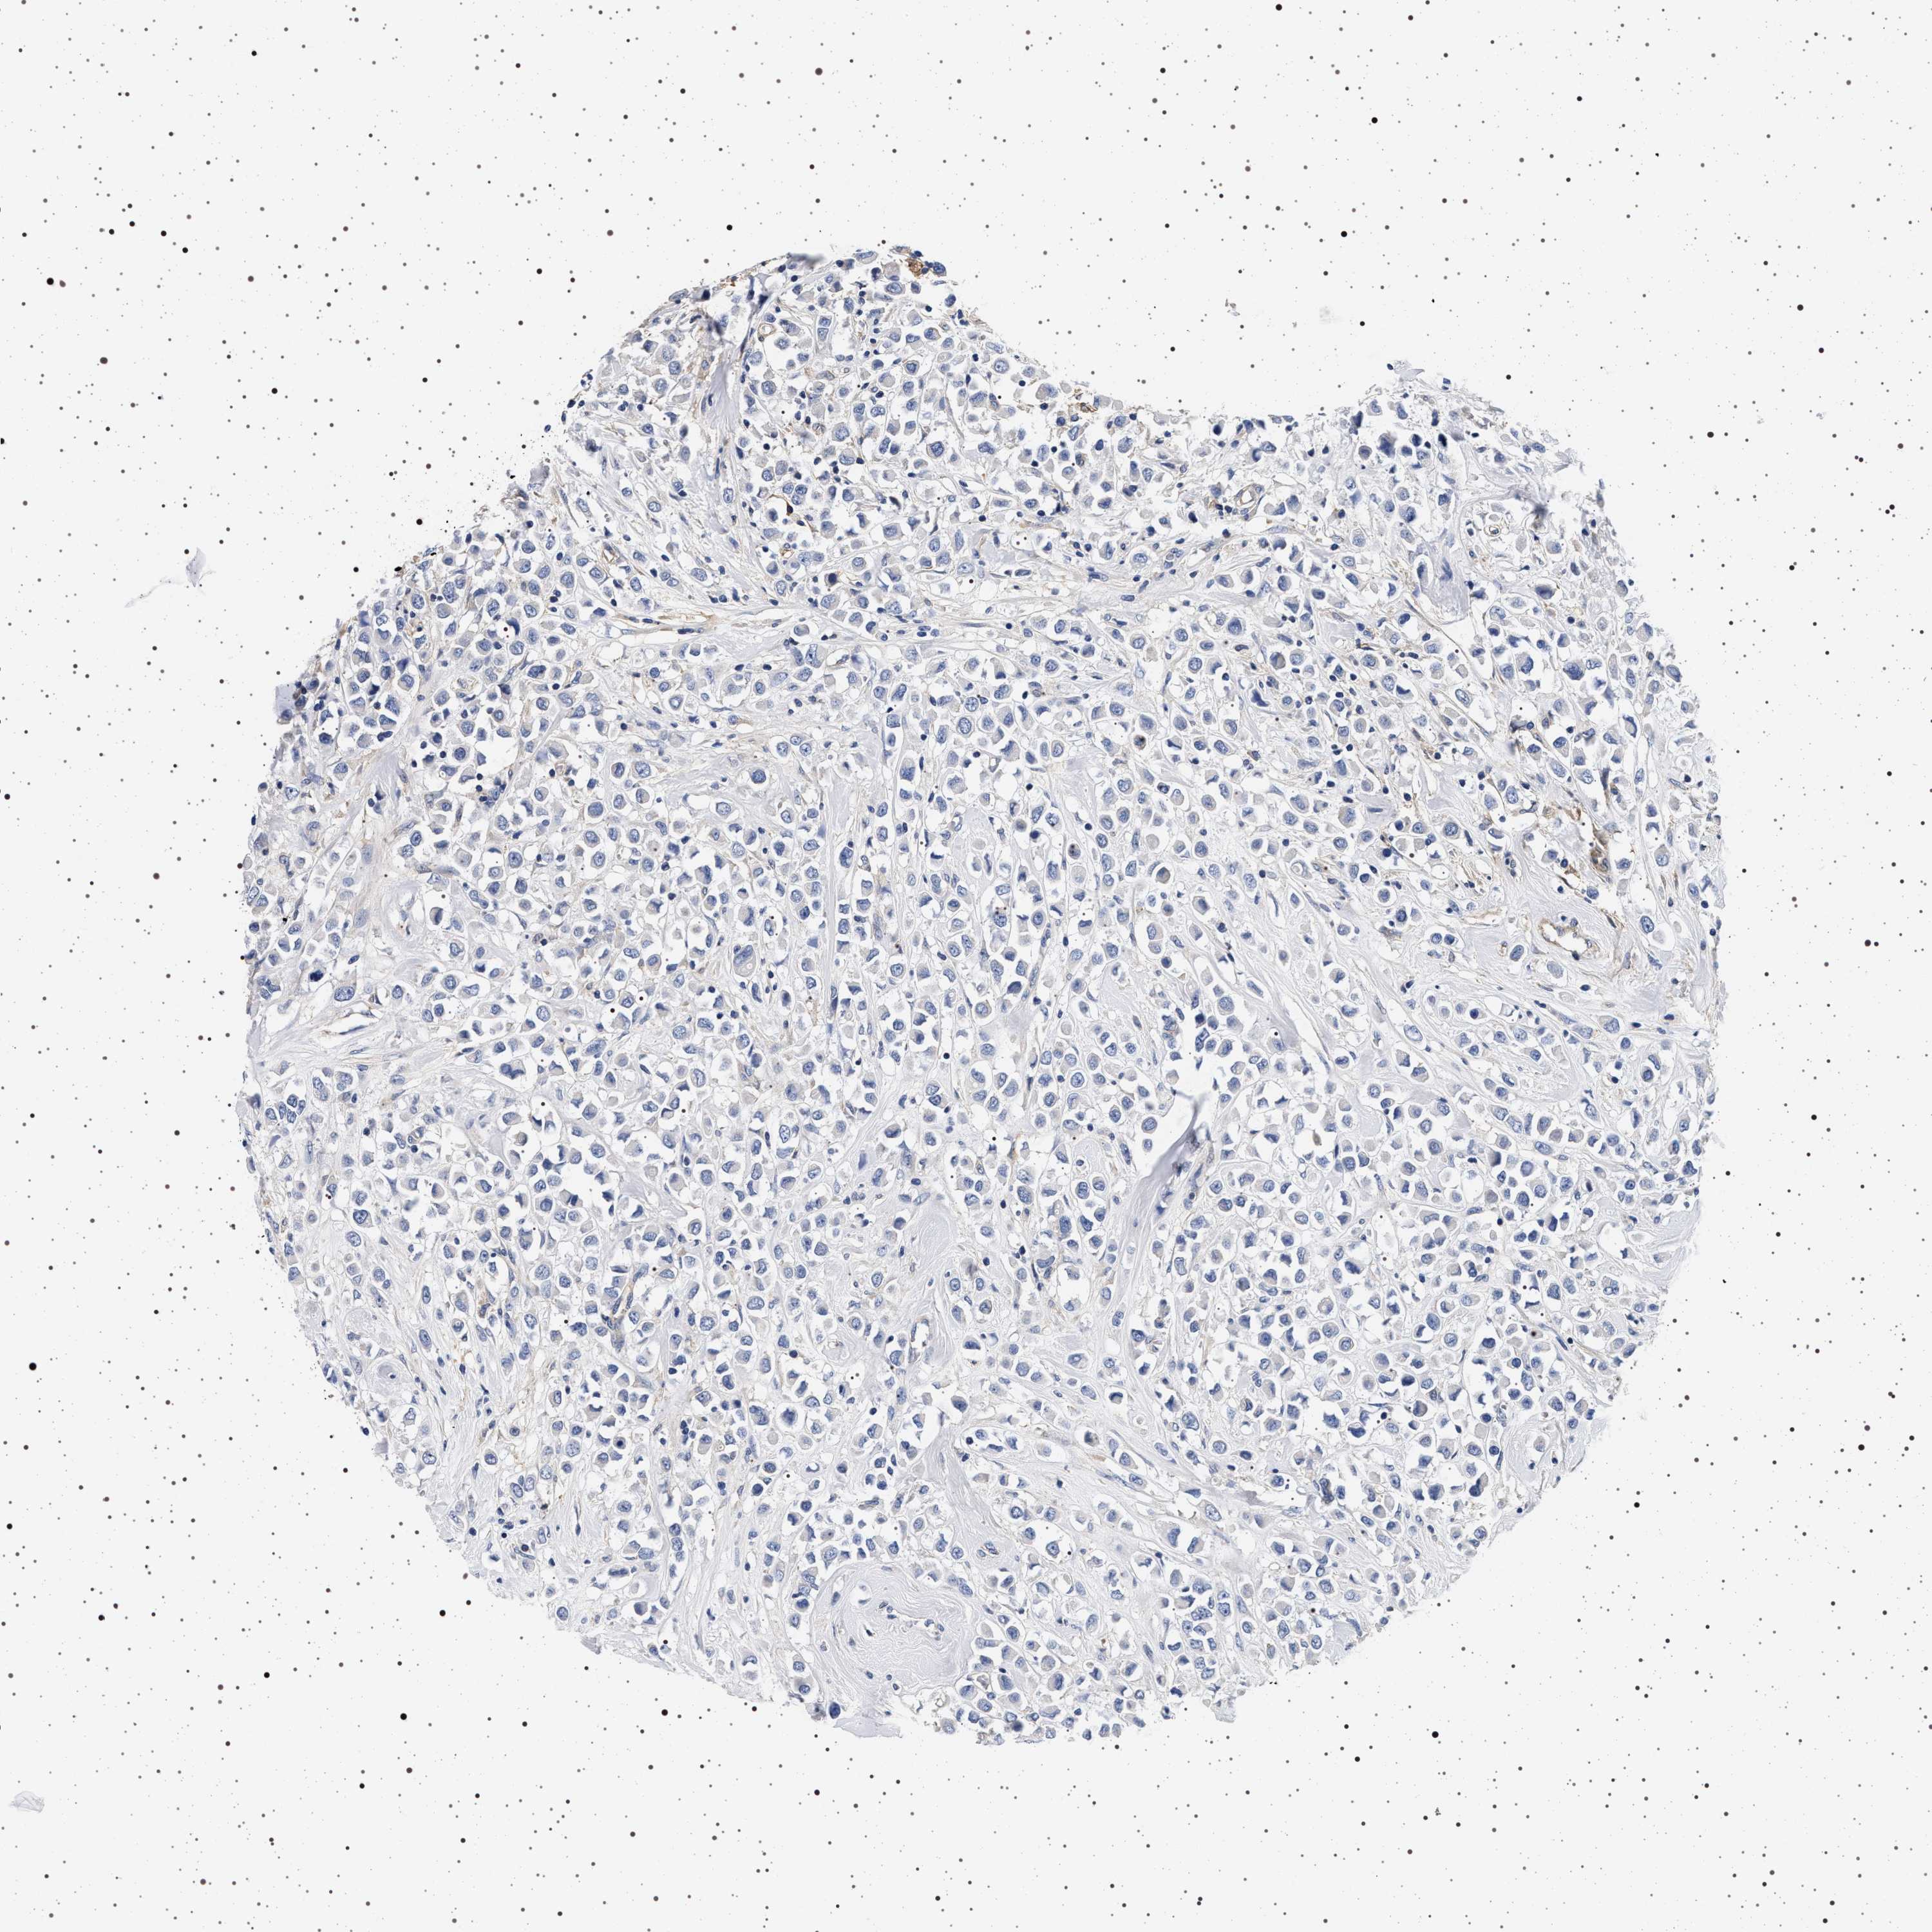

CANCER BREAST CANCER Show tissue menu

BRCA TCGA BRCA VALIDATION PROTEIN EXPRESSION